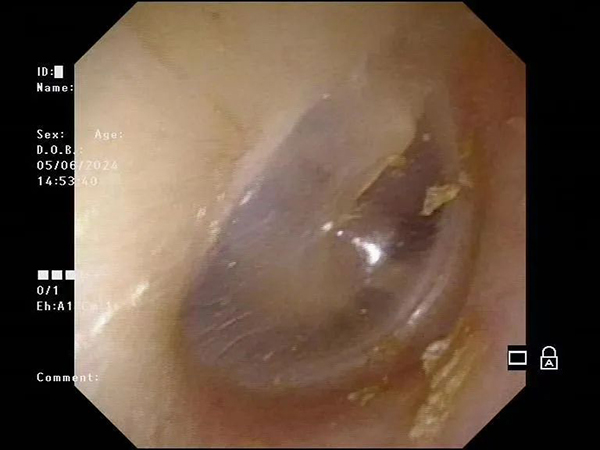

镜下影像示例:

镜下小儿鼓膜像